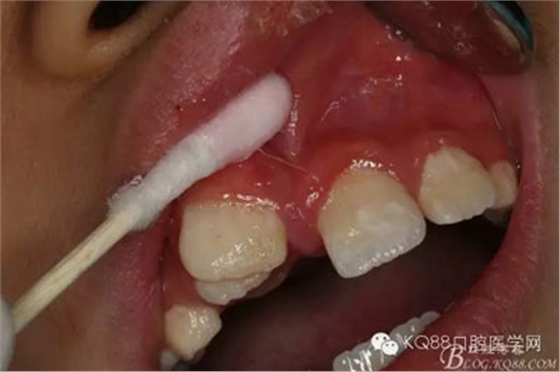

圖4.局部粘膜先涂表麻膏